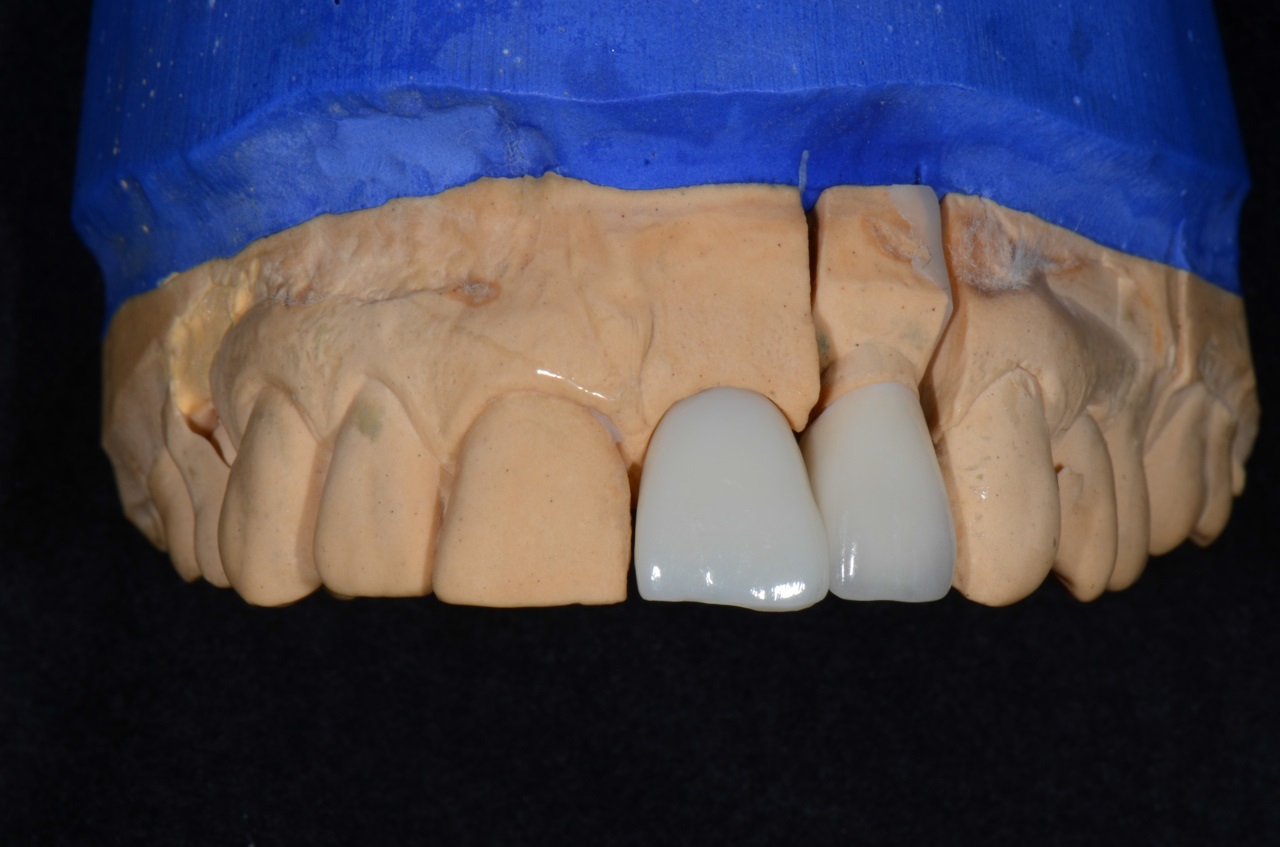

14/16 - Implant screwed crown for restoration of 21 and full porcelain crown for 22

Socket preservation with cerabone® - Dr. R. A. Nader